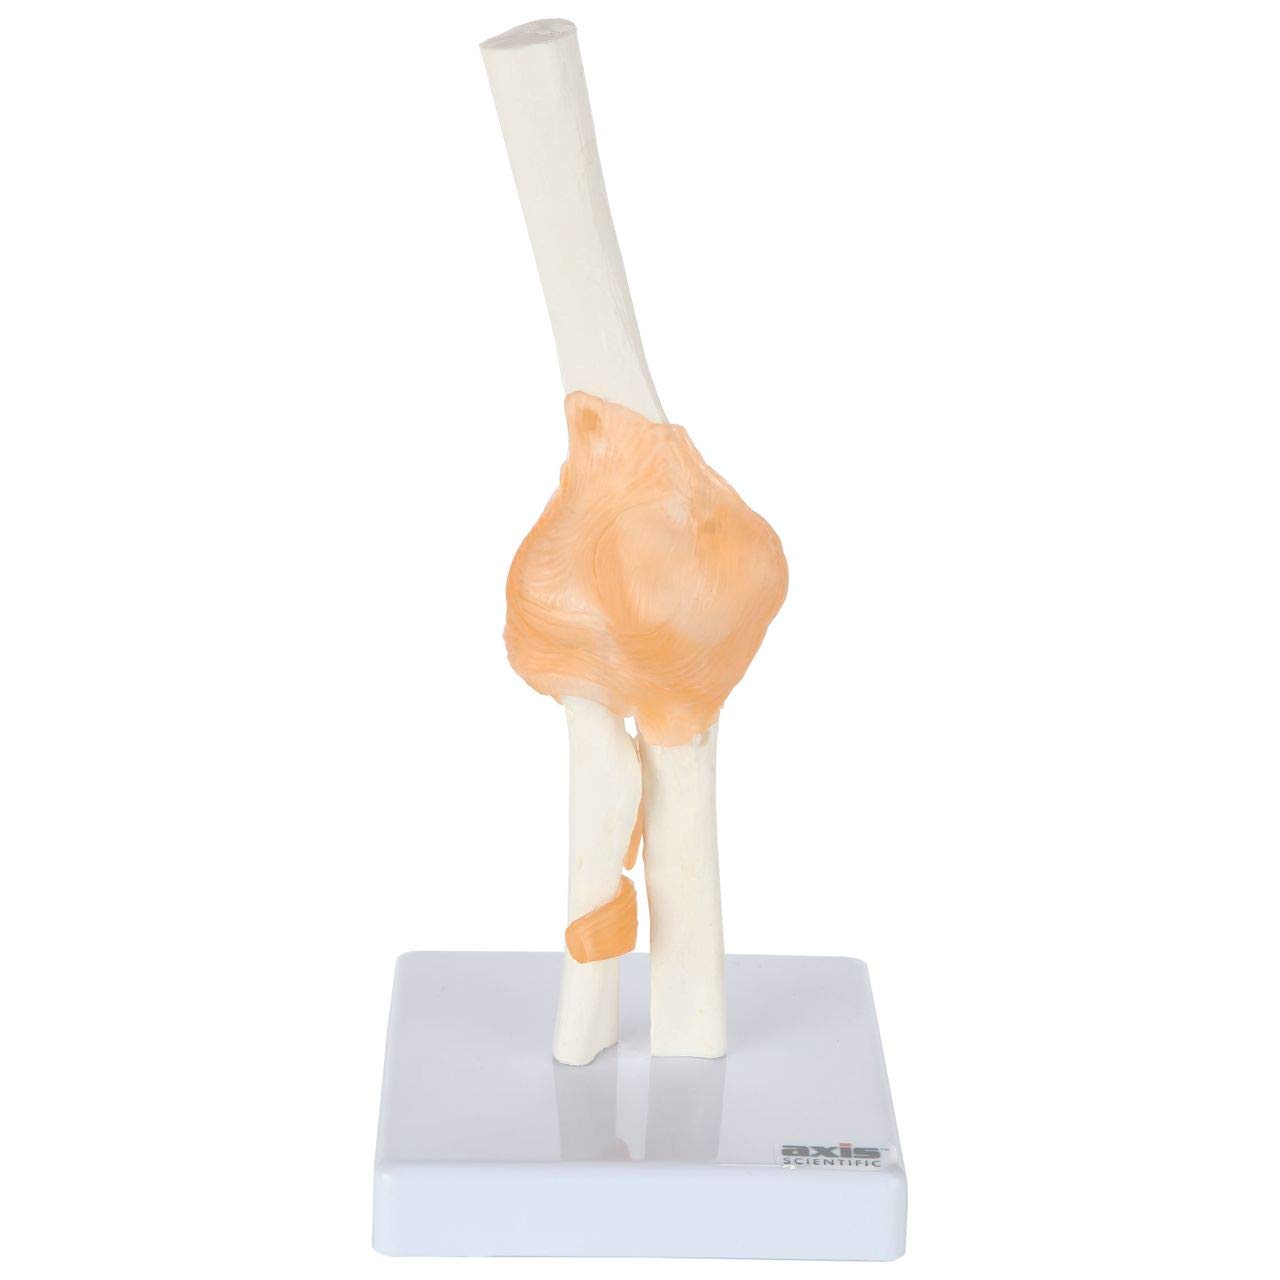

- Complete Human Joint Anatomy Model Bundled Set: This exceptional collection of functional anatomical models of human joints offers a great view of the articulation of the major joints in the human body and their connective ligaments. The set includes a life size knee model with ligaments, a flexible should joint model, a flexible hip joint model and a life size elbow joint model with ligaments: This fully functional joint anatomical models are an exceptional study aid for anyone looking to study movements of the human joints. The model can be bent to display the ligaments front and back, as well as reveal the connecting bones

- Interact and Learn: These functional joint anatomy models feature limited flexibility, while still maintaining the level of anatomical detail in the bony landmarks and the ligaments that Axis Scientific delivers with every model. The models are constructed with flexible plastic ligaments, each of which is attached with clear plastic, almost invisible, screws allowing for an uninterrupted view of the joints’ construction and come mounted on secure white bases

- High Quality Anatomical Model: Axis Scientific anatomy joint models are hand-painted and assembled with the utmost attention to detail. The removable parts are secured with a combination of hooks, magnets and pegs. Mounted on a sturdy base, this functional joint model makes a great demonstration and patient education tool. It is perfect for the doctor’s office, physical therapy clinic or anatomy classroom